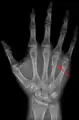

A fractured right hand fourth metacarpal (boxer's fracture).